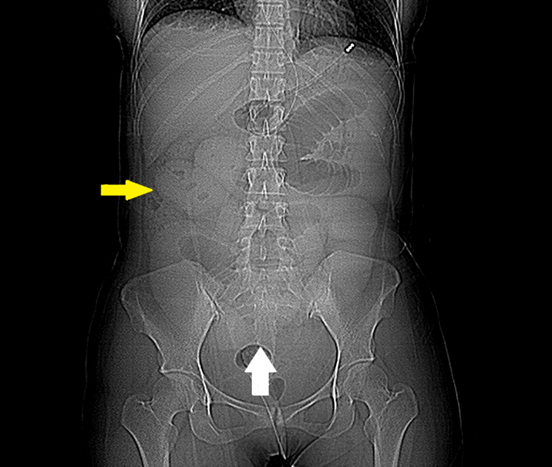

On physical examination, the abdomen was markedly distended with generalized tenderness and guarding. Laboratory investigations revealed an elevated C-reactive protein (CRP) level of 85 mg/L, hypokalemia (serum potassium 3.2 mmol/L), and hypocalcemia (serum calcium 1.98 mmol/L), while other hematological and biochemical parameters were within normal limits.Simple X-Ray of the Abdomen showed features of small bowel obstruction. [Figure 1]

Figure 1: Supine abdominal radiograph demonstrating dilated loops of proximal small bowel in the central part of abdomen, (yellow arrow), containing non-ionic oral contrast, consistent with small bowel obstruction. A transition point is noted in the mid pelvis position (white arrow), suggestive of a mechanical etiology.